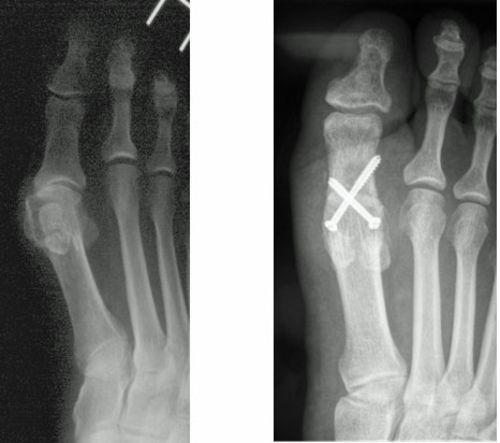

Abb.8: Korrektur des schmerzhaften Kleinzehenballen (Schneiderballen, Taylors bunion) durch die Kombination einer basisnahen Korrektur und einer Chevronette Osteotomie.

a Fehlstellungswinkel vor der Operation.

b Die Knochenachsen sind wieder parallel und der Vorfuß verschmälert.